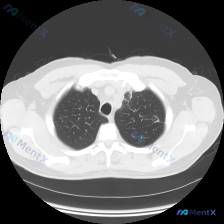

基本信息:患者的检查是胸部CT肺窗横断面,清晰度良好,无明显伪影,能较好显示肺实质结构。

主要表现:左肺上叶尖后段可见局限性的条索影及少许透亮度略微增高区域,边缘模糊,伴有细小的网格状影,局部肺纹理轻微扭曲或纠集。右肺上叶未见明显异常,气管管腔通畅,双肺透亮度基本对称。

初步判断:第一印象是这个病变可能是良性的陈旧性改变,但需要进一步分析鉴别。

推理收敛:综合来看,这个病变更倾向于良性的陈旧性病变,因为肺尖部是陈旧性结核的好发部位,局限性纤维条索影符合陈旧性改变的特点,而且没有典型的恶性征象。